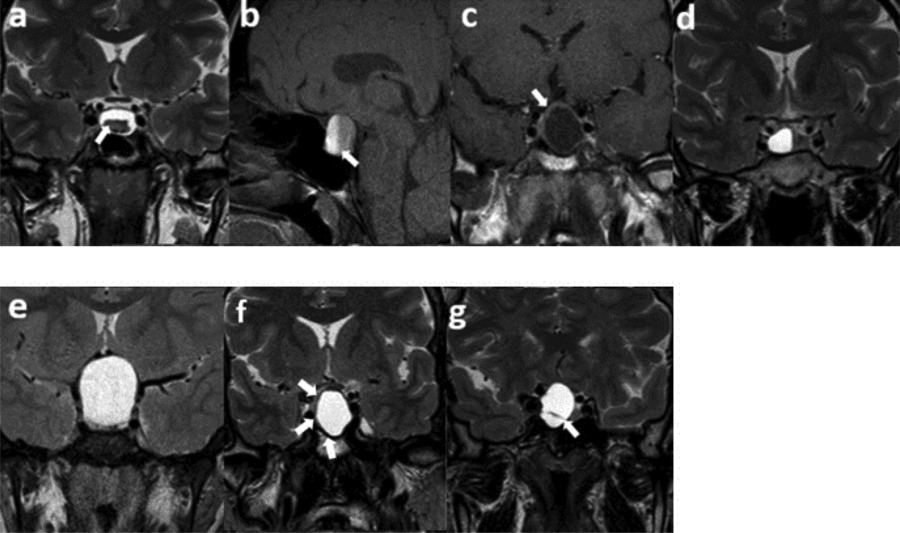

Two investigators blinded to the pathology results independently performed the initial semantic evaluation of the MRI. They assessed seven semantic features: intracystic nodules on T2WI, intralesional fluid-fluid levels on spectral presaturation with inversion recovery (SPIR) sagittal T1WI, contrast-enhancing walls with a minimum thickness of 2 mm on post-contrast T1WI, off-midline locations, suprasellar extensions, hypointense rims on T2WI, and intralesional septations on T2WI (Figure 1). These features were chosen due to their high reproducibility demonstrated in prior research [3,5,11]. An interobserver agreement analysis followed this initial assessment. If disagreements arose between the two observers, another senior observer with extensive experience in the field was consulted. The final decision was made by consensus.

Figure 1

Semantic features. (a) An intracystic nodule on T2WI, (b) intralesional fluid–fluid level on SPIR T1WI, (c) ≥2 mm thickness of contrast-enhancing wall, (d) off-midline location, (e) suprasellar extension, (f) hypointense rim on T2WI, (g) intralesional septation on T2WI.